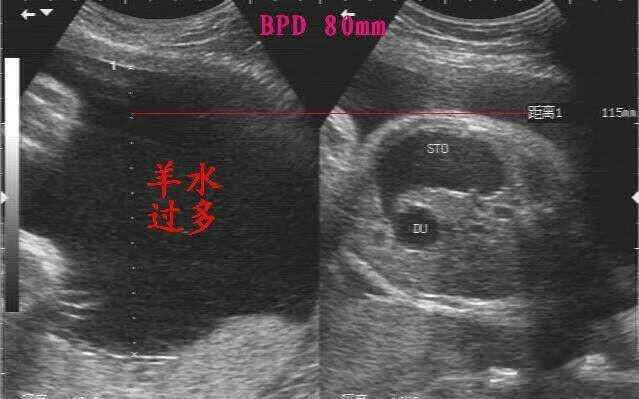

妊娠期间羊水量超过2000ml,称为羊水过多。发生率为0.5%~1%。羊水量在数日内急剧增多,称为急性羊水过多;羊水量在较长时间内缓慢增多,称为慢性羊水过多。羊水过多时羊水外观、形状与正常者无差异。